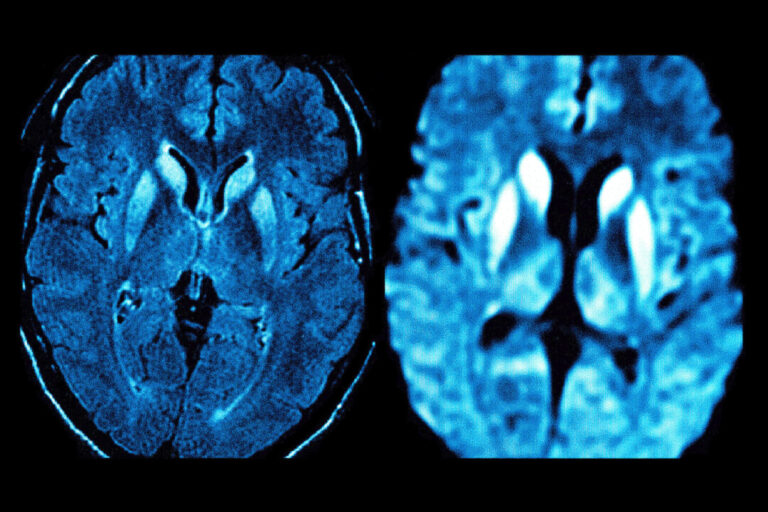

A brain scan of a patient with the degenerative disorder Creutzfeldt-Jakob disease (CJD). Health authorities say an unexplained brain illness investigated in New Brunswick has symptoms similar to CJD. (By BSIP/Getty Images